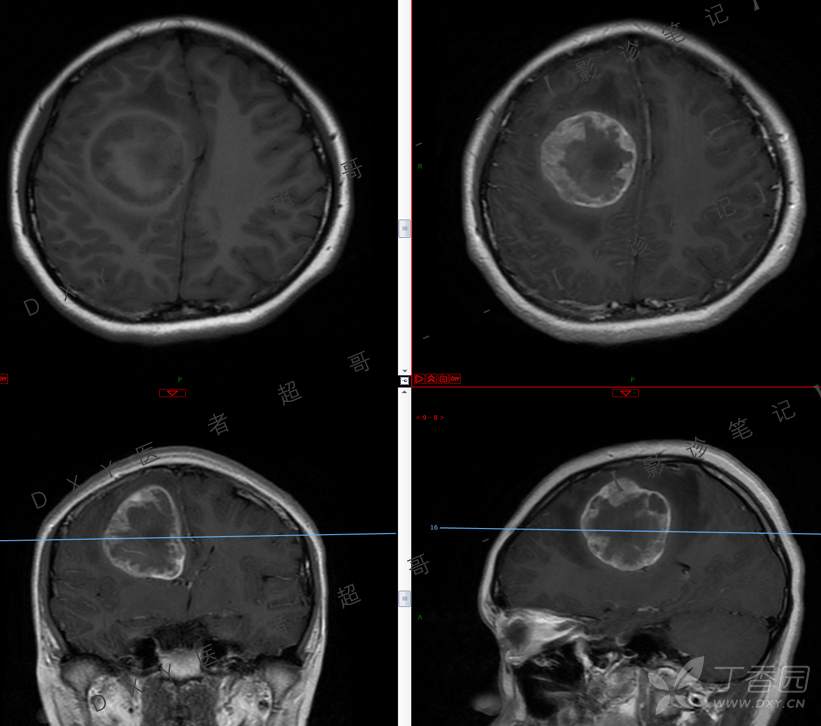

15岁少年,头痛10天,加重伴恶心、呕吐2天,究竟为何?回帖即可查阅病理。

患者年龄:15岁

主 诉:头痛10天,加重伴恶心、呕吐2天。

现病史:患者10天前无明显诱因出现头痛,间断发作,无恶心、呕吐,无肢体抽搐等,于当地医院就诊,体温37.4度,予以对症治疗,具体不详,后症状缓解,2天前患者上述症状较前加重,并感双眼胀痛及视物模糊,伴恶心、呕吐,呕吐数次,为胃内容物,再次于当地医院就诊,行颅脑CT考虑“右侧额顶叶病变”,现为求进一步治疗来我院急诊就诊,以“脑脓肿?”收入我科。患者病来精神差,饮食、睡眠欠佳,体重无明显变化。